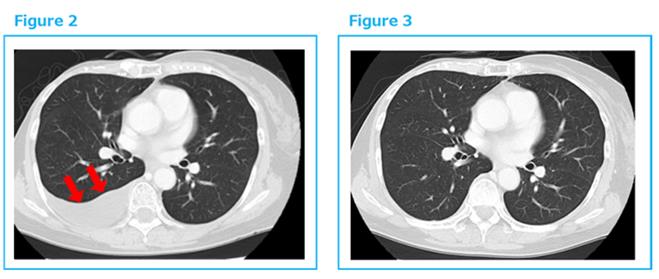

2014年底出现胸水,穿刺诊断复发。于是2015年1月再开始αβT细胞治疗,每2周1次共6次,之后每个月1次。到2016年3月胸水完全消失。